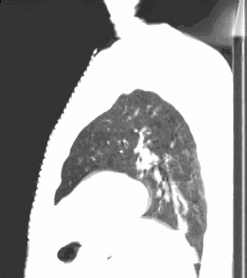

4D呼吸门控扫描

使用D4D呼吸门控扫描,可清楚观察到肿瘤本身随呼吸周期运动的情况。